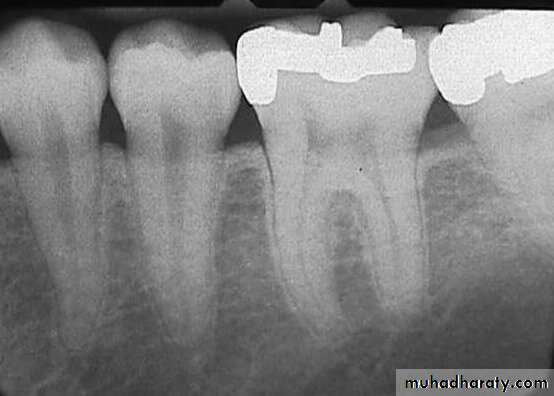

Teeth are composed of pulp (arrow on the secondmolar), enamel (arrow on the first molar), dentin (arrow onthe second premolar), and cementum (usually not visibleradiographically).

Radiographic Anatomy Basics: The Tooth

Radiographic Anatomy Basics